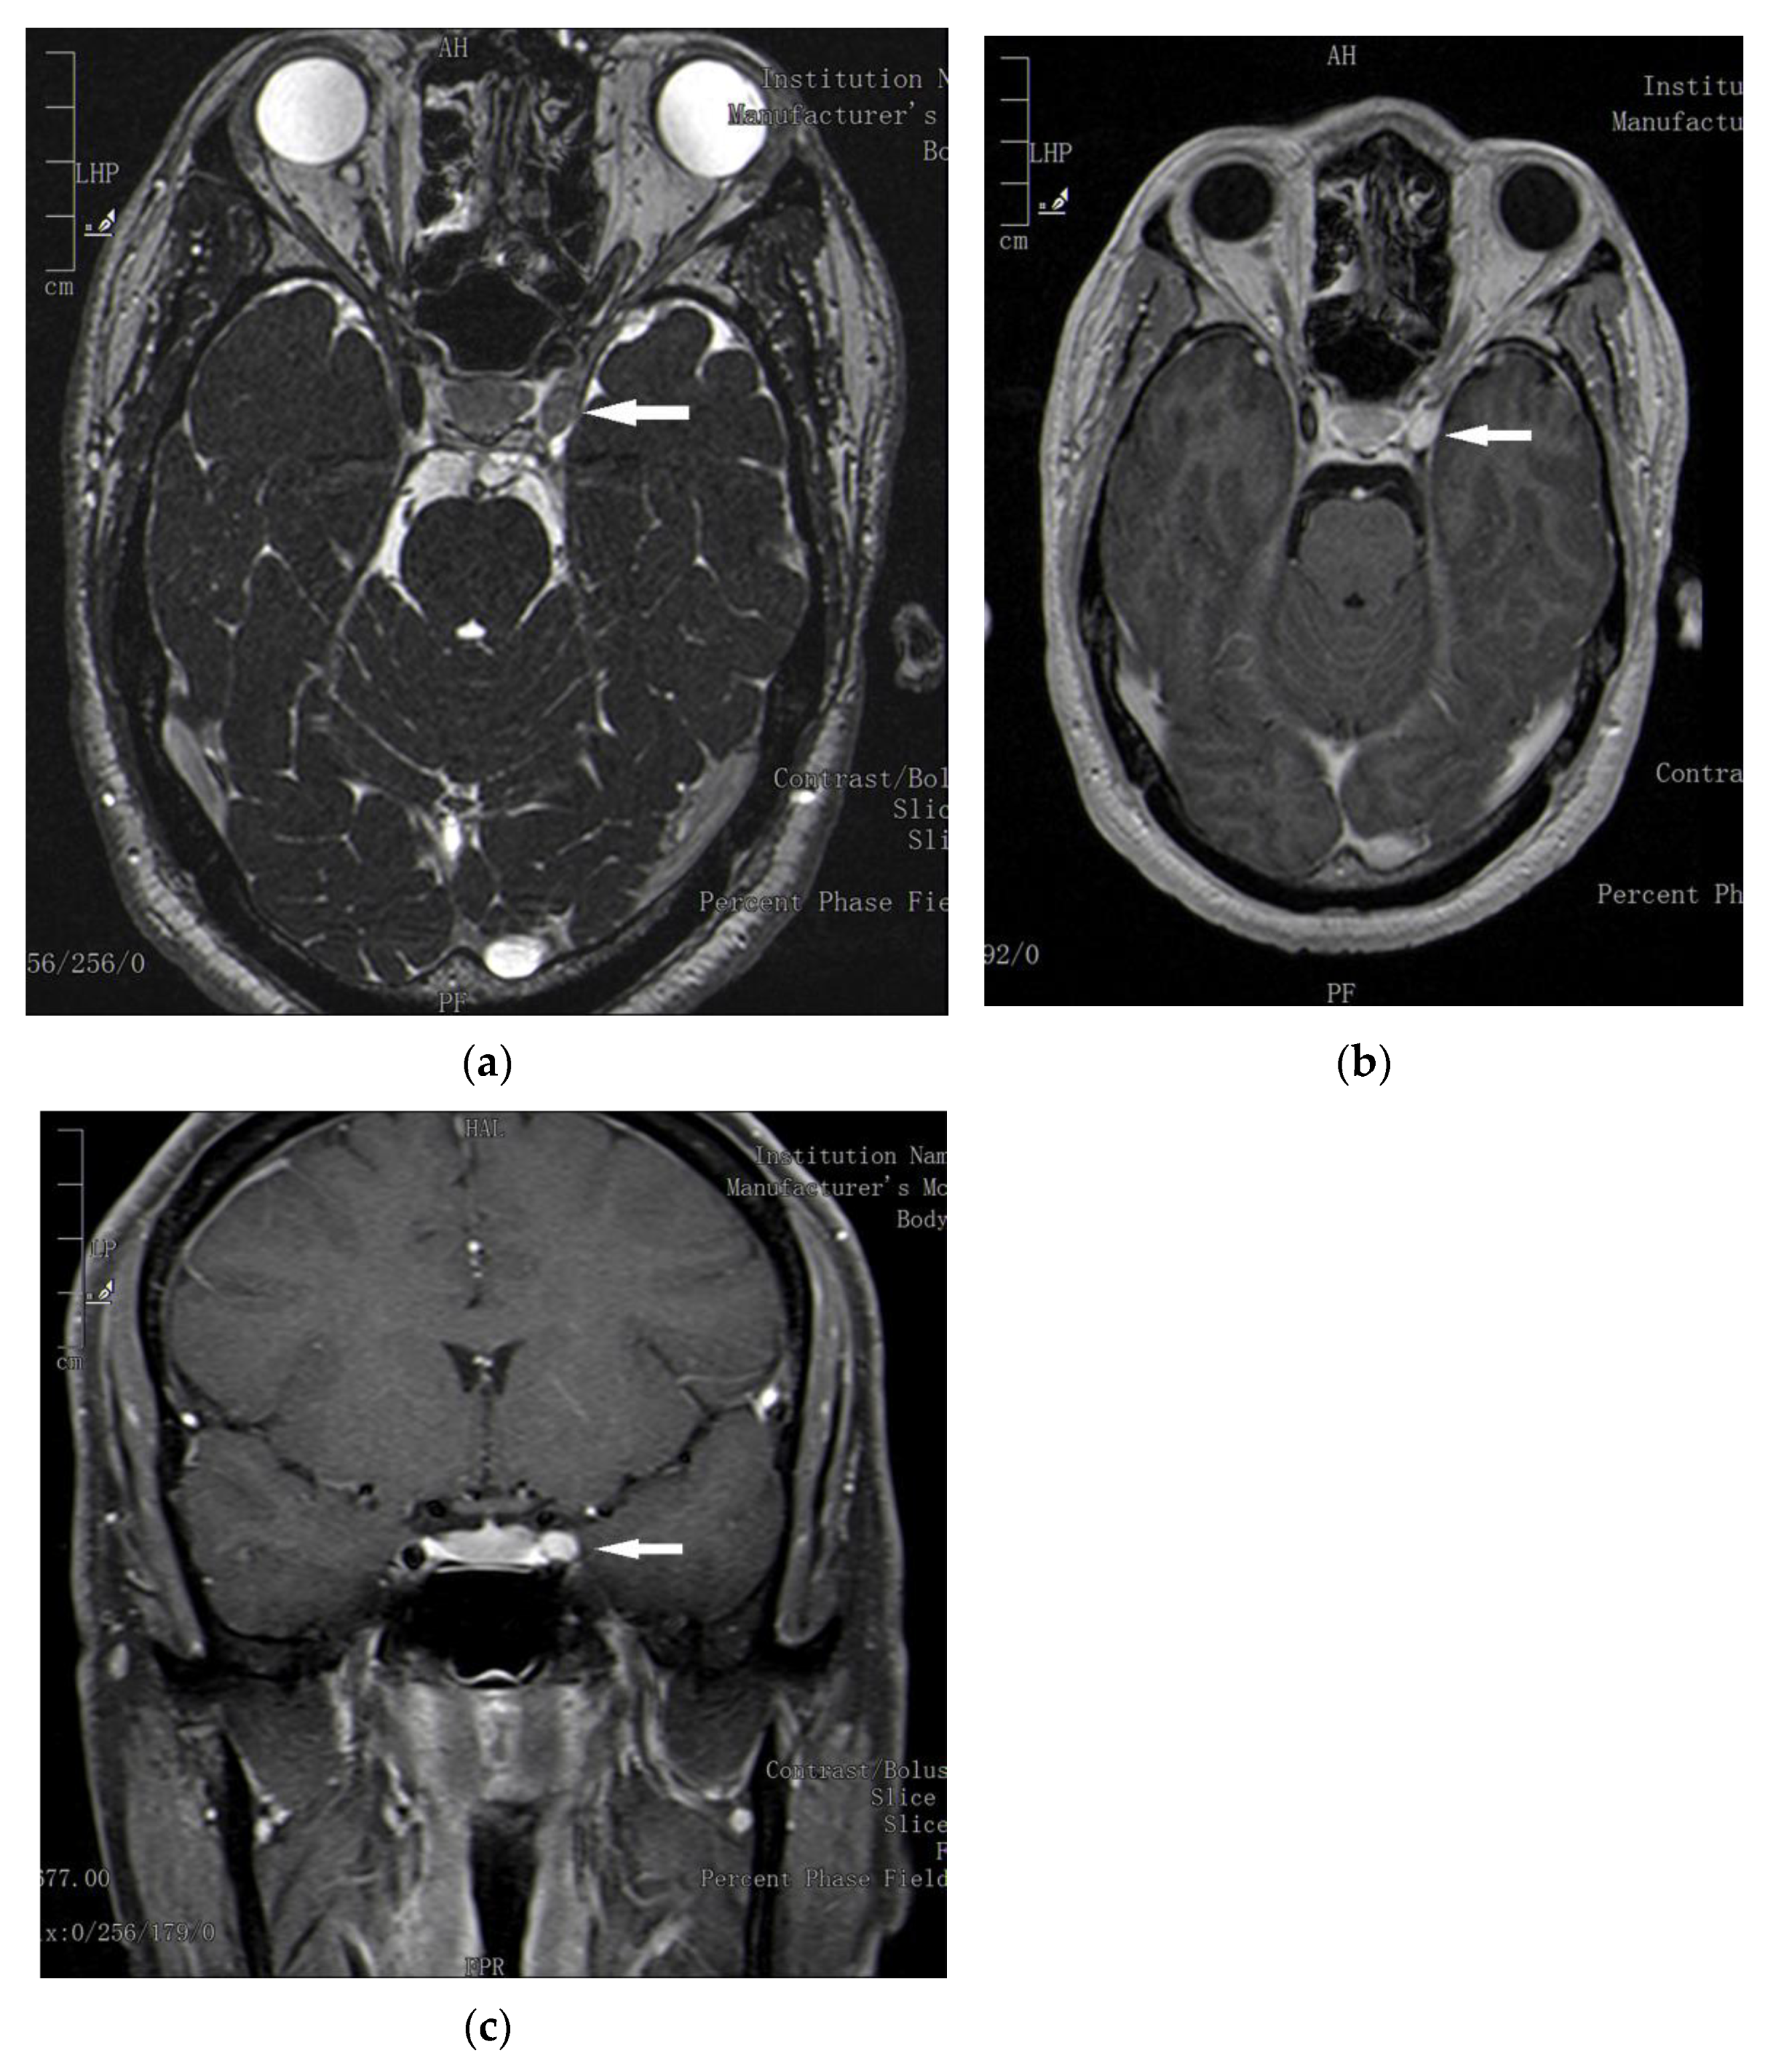

2. Case Report